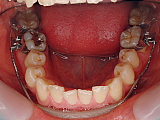

初診時の状態です。上下の歯並びがガタガタしています。